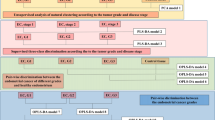

Borderline ovarian tumour tissue is often difficult to discriminate from carcinoma as they share many similar characteristics. As such, it would be beneficial to develop robust tools to accurately identify borderline tumours by characterising their shifting metabolism towards carcinoma. Multivariate analysis of normal, borderline and carcinoma samples was performed, and the results are shown in Fig. 5a and b.

Statistical analysis of DESI MS spectra between 600–1000 Da from two different perspectives: all carcinomas together, borderline ovarian tumours and normal stroma from normal ovary (a and b) and from the different carcinomas as serous, endometrioid and clear cell carcinomas together with normal stroma from normal ovary (c and d). (a and c) shows maximum margin criteria analysis (RMMC) cross validated and (b) and (d) shows leave-one-patient-out cross validation results.

Supervised analysis in Fig. 5a shows a much clearer continuum from normal to carcinoma, through borderline, tissue types. The confusion matrix in Fig. 5b shows an overall accuracy of 91%, with none of the misclassifications being between the carcinoma and normal pixels.

Borderline tumours can be difficult to diagnose, which may explain the borderline tumour samples being misclassified as carcinoma and vice versa23. The supervised classification results point to there being differences in the lipidomic profiles across the continuum of these three tissue groups. This represents altered metabolism in these tissues and may give insight into the underlying biological mechanisms responsible for the pathogenesis of malignancy in ovarian tissue.

Serous carcinomas are the most common type of EOC, followed by endometrioid, clear cell and mucinous carcinomas, which explains the lower sample number in the non-serous groups (Table 1). Multivariate comparisons of three carcinoma groups (endometrioid, clear cell and serous carcinomas) are shown in Fig. 5c and d along with normal ovarian tissue. From a lipidomic perspective, serous carcinoma is highly distinct from both clear cell and endometrioid carcinomas. However, these latter two are essentially indistinguishable from each other when comparing their lipidomic profiles.